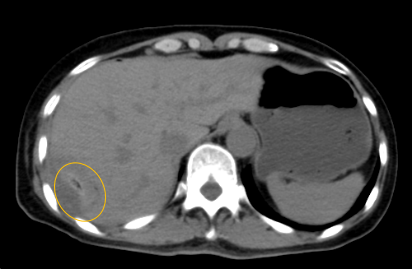

入院后,影像診療中心立即給李女士完善了CT和MR檢查,發(fā)現(xiàn)病變位于肝包膜下,臨近膈肌,消融治療過程中有并發(fā)損傷膈肌的可能,難度較大,但是采用精準影像定位是可以完成的。陳寶瑩主任立即與腫瘤三病區(qū)劉金鵬主任聯(lián)系,并與影像微創(chuàng)治療小組進行MDT討論:患者為卵巢癌肝右葉包膜下單發(fā)轉(zhuǎn)移瘤,最長徑不超過3cm,患者對局部治療的主觀愿望強烈,符合消融治療專家共識,遂制定了影像引導(dǎo)下局部消融治療聯(lián)合全身治療的綜合治療方案。

針對這個特殊部位的腫瘤,要想消融完全,那么膈肌損傷的風險就很高,陳寶瑩主任帶領(lǐng)影像微創(chuàng)亞專業(yè)組成員仔細閱讀CT圖像,設(shè)計進針路徑,結(jié)合MR圖像確定腫瘤活性范圍,制定了周密而詳盡的消融計劃。臘月二十九,即住院第二天影像微創(chuàng)治療小組圓滿為患者完成了腫瘤微波消融治療,觀察24小時后出院回家過年。術(shù)后48小時隨訪患者無明顯不適,術(shù)后7天隨訪,患者肝功、血常規(guī)等各項指標均恢復(fù)正常。